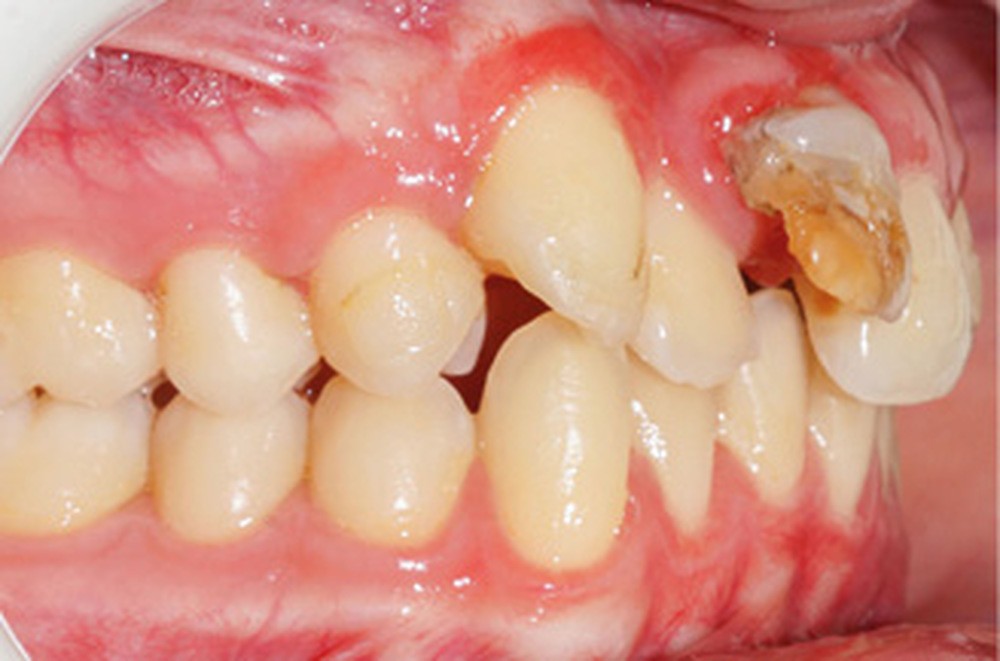

Son incisive centrale supérieure droite (11) présente un défaut de structure amélaire sévère, compromettant une technique restaurative pérenne a minima. L’examen de la panoramique (fig. 1e) et de la radiographie rétroalvéolaire de 11 (fig. 1f) objective une fracture coronaire verticale, ainsi qu’une racine grêle et courbe, peut-être en rapport avec un ancien traumatisme [1]. Le rapport couronne clinique/racine clinique est défavorable.